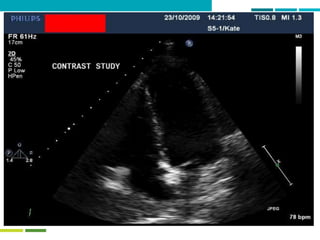

Two mechanisms of bubble formation –

with a twist!

BUBBLE FORMATION

Dissolved gas Pulmonary barotrauma

Venous blood Arterial bloodTissues

Patent foramen ovale + other shunts